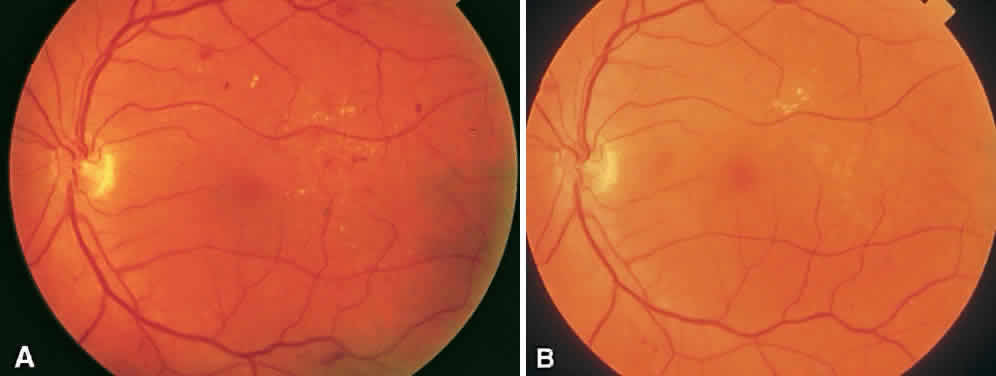

CSME was defined as retinal thickening within 500 μm of the center of the macula, intraretinal hard exudate within 500 μm of the center of the macula associated with adjacent retinal thickening, or retinal thickening greater than one disc area any part of which is within one disc diameter of the center of the macula (Fig. 3A). The beneficial effects of treatment demonstrated in this trial suggest that all eyes with CSME should be considered for focal photocoagulation (see Fig. 3B). Visual acuity was not a factor in determining the presence or absence of CSME and some eyes in the treated group had20/20 visual acuity. Many retinal specialists, how-ever, defer treatment in asymptomatic patients with20/20 visual acuity except when hard exudate is encroaching on the fovea.